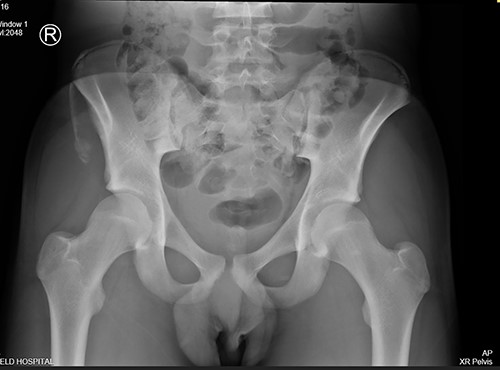

The anterior–posterior plain film X-Ray of pelvis demonstrated an avulsion fracture of the right ASIS and IC apophysis with 1.5 cm displacement (Fig. 1). Lateral view of the hip showed no extension into the joint. There was no radiological evidence of chronic overuse or previous injury. Computed tomography (CT) imaging was performed to better identify the injury; 3D volume reconstruction clearly demonstrated the unique fracture pattern of an ASIS avulsion in addition to an avulsion of the distal iliac apophysis extending ~5 cm with the described displacement (Figs 2–4).

AP radiograph following injury, demonstrating a large avulsion from the right hemipelvis, including the ASIS and portion of the IC apophysis (R - Right).